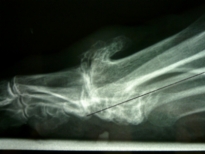

C'est une arthrose de l‘articulation de la base du premier orteil sans déviation de l’orteil (arthrose dans l’axe).